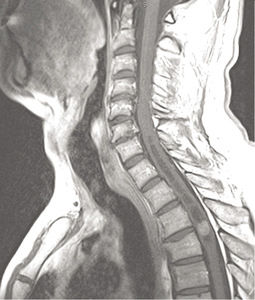

Podstawowym badaniem pozwalającym wykryć guza śródrdzeniowego jest obrazowanie rezonansem magnetycznym (MR) (ryc. 1, 2). Badanie to wykonywane jest w czasie T1 i T2 zależnym, bez podania środka kontrastowego i po jego zastosowaniu. Najbardziej przydatne jest obrazowanie w trzech projekcjach: strzałkowej, poprzecznej i czołowej.9